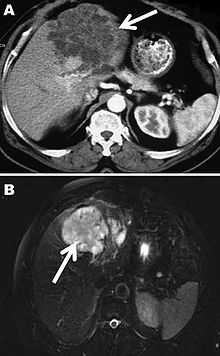

L'échinococcose alvéolaire est une maladie grave qui se développe lentement, essentiellement au niveau du foie, sur plus de 15 ans, et de manière asymptomatique. Se traduisant par une hépatomégalie, des douleurs abdominales, un ictère et une fièvre, elle était autrefois souvent confondue avec la cirrhose ou le cancer du foie. La symptomatologie est atypique chez 1/3 environ des patients, avec douleurs abdominales isolées chez 1/3 environ des patients, le dernier tiers présentant une association de symptômes : douleurs abdominales (90 % des cas), hépatomégalie (61 %), altération modérée de l’état général (48 %), ictère, subictère ou prurit (41 %). Il existe une corrélation entre les symptômes et la localisation des lésions[8]. La forme cystique concerne essentiellement le foie et le poumon. La croissance des parasites est longue, sur plusieurs années et le patient est très souvent asymptomatique au début de l'atteinte (ne se plaint d'aucun signe). Les signes apparaissent soit en raison d'une compression d'un organe, soit en raison d'une complication, rupture ou infection. La rupture, tout comme une exérèse mal conduite, peut se compliquer d'une dissémination des kystes à d'autres endroits de l'organisme.

Un diagnostic peut être effectué par la détection des anticorps spécifiques au parasite dans le sang du patient (test remboursé par l’Institut national d'assurance maladie invalidité belge)[9], et en cas de résultat positif être confirmé par imagerie médicale[10].